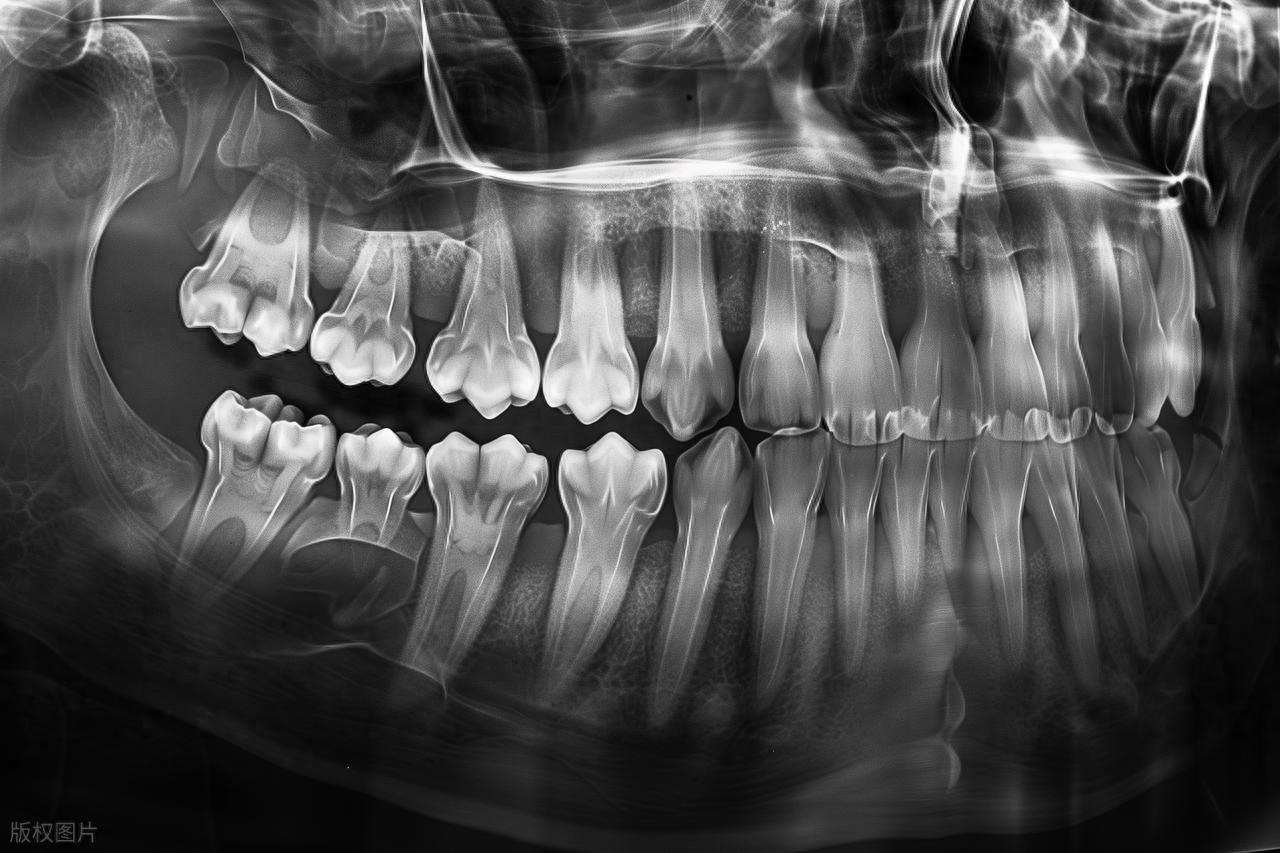

2.易出現阻生情況

由於頜骨空間不足,智齒很容易出現阻生現象,即智齒不能正常萌出或萌出位置不正。常見的阻生類型包括水平阻生、近中阻生、垂直阻生等。阻生的智齒可能只露出一部分牙冠,或者完全埋伏在牙齦下方,這不僅會導致萌出過程中的不適,還可能引發其他口腔問題。

如果智齒能夠正常萌出,位置和方向良好,能夠正常行使咀嚼功能,並且在日常口腔清潔中能夠被有效清潔,沒有出現任何不適症狀,那麼通常不需要進行特殊處理,只需定期進行口腔檢查,關注其生長情況即可。

如果智齒在萌出過程中反覆出現牙齦發炎、疼痛,或者出現食物嵌塞、鄰牙齲壞、牙根吸收等問題,或者經檢查發現智齒存在明顯的阻生情況,那麼建議及時就醫諮詢專業口腔醫生。醫生會根據具體情況進行評估,判斷是否需要採取相應的處理措施。